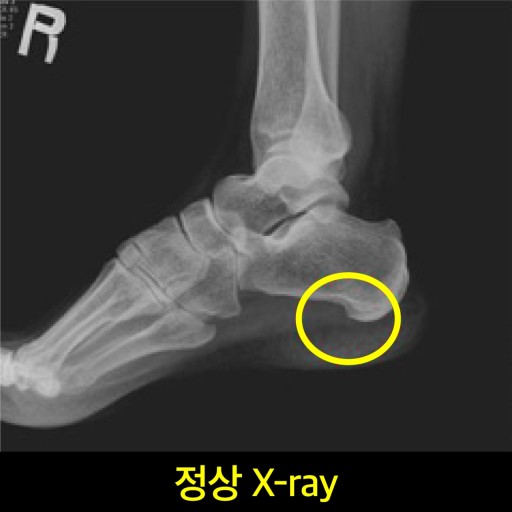

1. 족저근막염

가장 흔한 원인 중 하나로,

발바닥 아치 밑을 지탱하는 족저근막에 염증이 생긴 상태입니다.

특히 아침에 첫발 디딜 때 극심한 통증이 느껴지며,

걷다 보면 통증이 조금 완화되지만 반복적으로 악화됩니다.